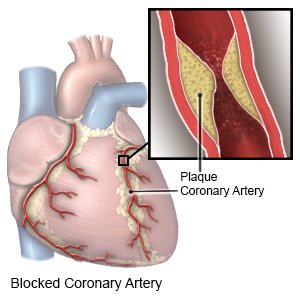

Overview

Package includes:

Days in hospital : 1 Day (For patient and one attendant)

Days in hotel : 2 Days (For patient and one attendant)

Room type in hospital : Shared

Room type in hotel : Private

Hotel category: Standard

Value added benefits of the Angiography:

Ø Doctor consultation charges

Ø Lab tests and diagnostic charges

Ø Room charges inside hospital during the procedure

Ø Surgeon Fee

Ø Nursing charges

Ø Hospital surgery suite charges

Ø Anesthesia charges

Ø Routine medicines and routine consumables (bandages, dressings etc.)

Ø Food and Beverages inside hospital stay for patient and one attendant.

Extra benefits:

ü Interpreter

ü Visa assistance

Ø Site tourism of the city

Ø Follow up with the doctor

Ø Airport pick up and drop

Ø Free online consultation with the doctor

Ø Priority appointments with the doctor

Ø Room upgrade from sharing to private

Overview

Package includes:

Days in hospital : 1 Day (For patient and one attendant)

Days in hotel : 2 Days (For patient and one attendant)

Room type in hospital : Shared

Room type in hotel : Private

Hotel category: Standard

Value added benefits of the Coronary Angiogram:

Ø Doctor consultation charges

Ø Lab tests and diagnostic charges

Ø Room charges inside hospital during the procedure

Ø Surgeon Fee

Ø Nursing charges

Ø Hospital surgery suite charges

Ø Anesthesia charges

Ø Routine medicines and routine consumables (bandages, dressings etc.)

Ø Food and Beverages inside hospital stay for patient and one attendant.

Extra benefits:

ü Interpreter

ü Visa assistance

Ø Site tourism of the city

Ø Follow up with the doctor

Ø Airport pick up and drop

Ø Free online consultation with the doctor

Ø Priority appointments with the doctor

Ø Room upgrade from sharing to private